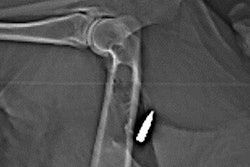

MRI of nonferromagnetic ballistics suspended in gelatin. Scout (A), T1-weighted spin-echo; (B), T2-weighted SE (C); T2-weighted gradient-recalled echo; (D), and T2-weighted gradient-recalled echo; (E) MR images show jacket hollow point .45 automatic Colt pistol bullet (1), solid lead .45 Long Colt bullet (2), full metal jacket automatic Colt pistol bullet (3), 5.56-mm full metal jacket bullet (4), #7 lead shotgun pellet (5), and 5-mm lead air gun pellet (6). On all sequences, metallic artifact is minimal. Images and caption courtesy of the American Roentgen Ray Society (ARRS).X-ray and CT images helped determine bullet fragment composition by identifying the presence or absence of a debris trail. They also indicated that ferromagnetic bullets showed mild torque forces and imaging artifacts, while nonferromagnetic bullets did not show these effects. None of the bullets visualized on MRI heated the gelatin higher than the U.S. Food and Drug Administration limit of 35.6○ Fahrenheit.